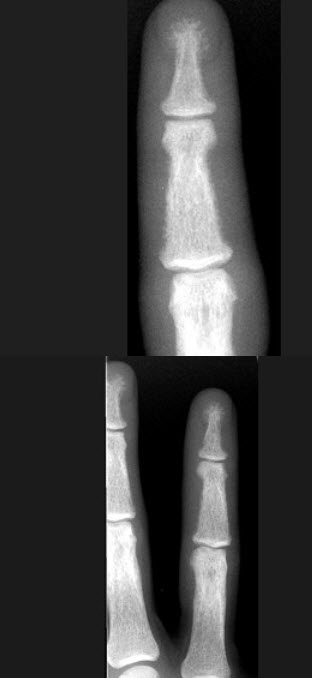

女,41岁,慢性肾功能不全,结合图像,最可能的诊断是( )

A:白血病

B:甲状旁腺功能亢进

C:地中海贫血

D:镰状细胞贫血

E:骨关节结核